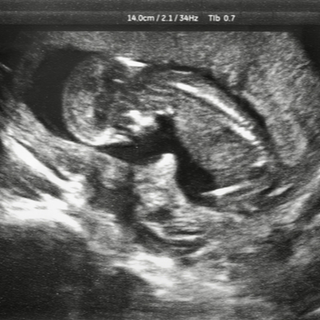

تطور وجه الجنين خلال الحمل في الشهر الثاني

تستمر ملامح وجه الجنين بالتكون خلال الحمل في الشهر الثاني، فتظهر الأذنان على شكل طيتان صغيرتان على الرأس، وتبدأ العيون والأنف بالتكون، مع بدء تكون القدرة على الشم.

تطور الجسم الخارجي للجنين خلال الحمل في الشهر الثاني

تنمو الأطراف في الشهر الثاني من الحمل مكونةً الذراعين والساقين، وتظهر الأصابع بشكل مكفف، ويكتمل نمو الأنبوب العصبي خلال الشهر الثاني.

تطور الأعضاء الداخلية للجنين خلال الحمل في الشهر الثاني

يكتمل نمو الأنبوب العصبي، ويبدأ كلًا من الجهاز العصبي والجهاز الهضمي بالنمو، وتبدأ العظام بالحلول مكان الغضاريف.

حركة الجنين خلال الحمل في الشهر الثاني

بالرغم من عدم شعور الحامل بالجنين، إلا أن الجنين يبدأ بالتحرك والركل باستخدام أطرافه حديثة النمو في الشهر الثاني.

طول ووزن الجنين في نهاية الشهر الثاني من الحمل

يصل طول الجنين مع نهاية الشهر الثاني من الحمل إلى ما يقارب 2.54 سنتمتر، ويزن تقريبًا 9.45 غرام.